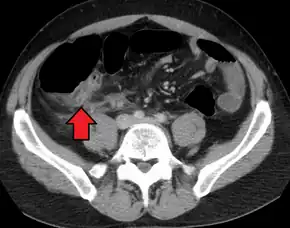

A fecalith marked by the arrow that has resulted in acute appendicitis.

Where it is readily available, computed tomography (CT) has become frequently used, especially in people whose diagnosis is not obvious on history and physical examination. Although some concerns about interpretation are identified, a 2019 Cochrane review found that sensitivity and specificity of CT for the diagnosis of acute appendicitis in adults was high.[59] Concerns about radiation tend to limit use of CT in pregnant women and children, especially with the increasingly widespread usage of MRI.[60][61]

The accurate diagnosis of appendicitis is multi-tiered, with the size of the appendix having the strongest positive predictive value, while indirect features can either increase or decrease sensitivity and specificity. A size of over 6 mm is both 95% sensitive and specific for appendicitis.[62]

However, because the appendix can be filled with fecal material, causing intraluminal distention, this criterion has shown limited utility in more recent meta-analyses.[63] This is as opposed to ultrasound, in which the wall of the appendix can be more easily distinguished from intraluminal feces. In such scenarios, ancillary features such as increased wall enhancement as compared to adjacent bowel and inflammation of the surrounding fat, or fat stranding, can be supportive of the diagnosis. However, their absence does not preclude it. In severe cases with perforation, an adjacent phlegmon or abscess can be seen. Dense fluid layering in the pelvis can also result, related to either pus or enteric spillage. When patients are thin or younger, the relative absence of fat can make the appendix and surrounding fat stranding difficult to see.[63]